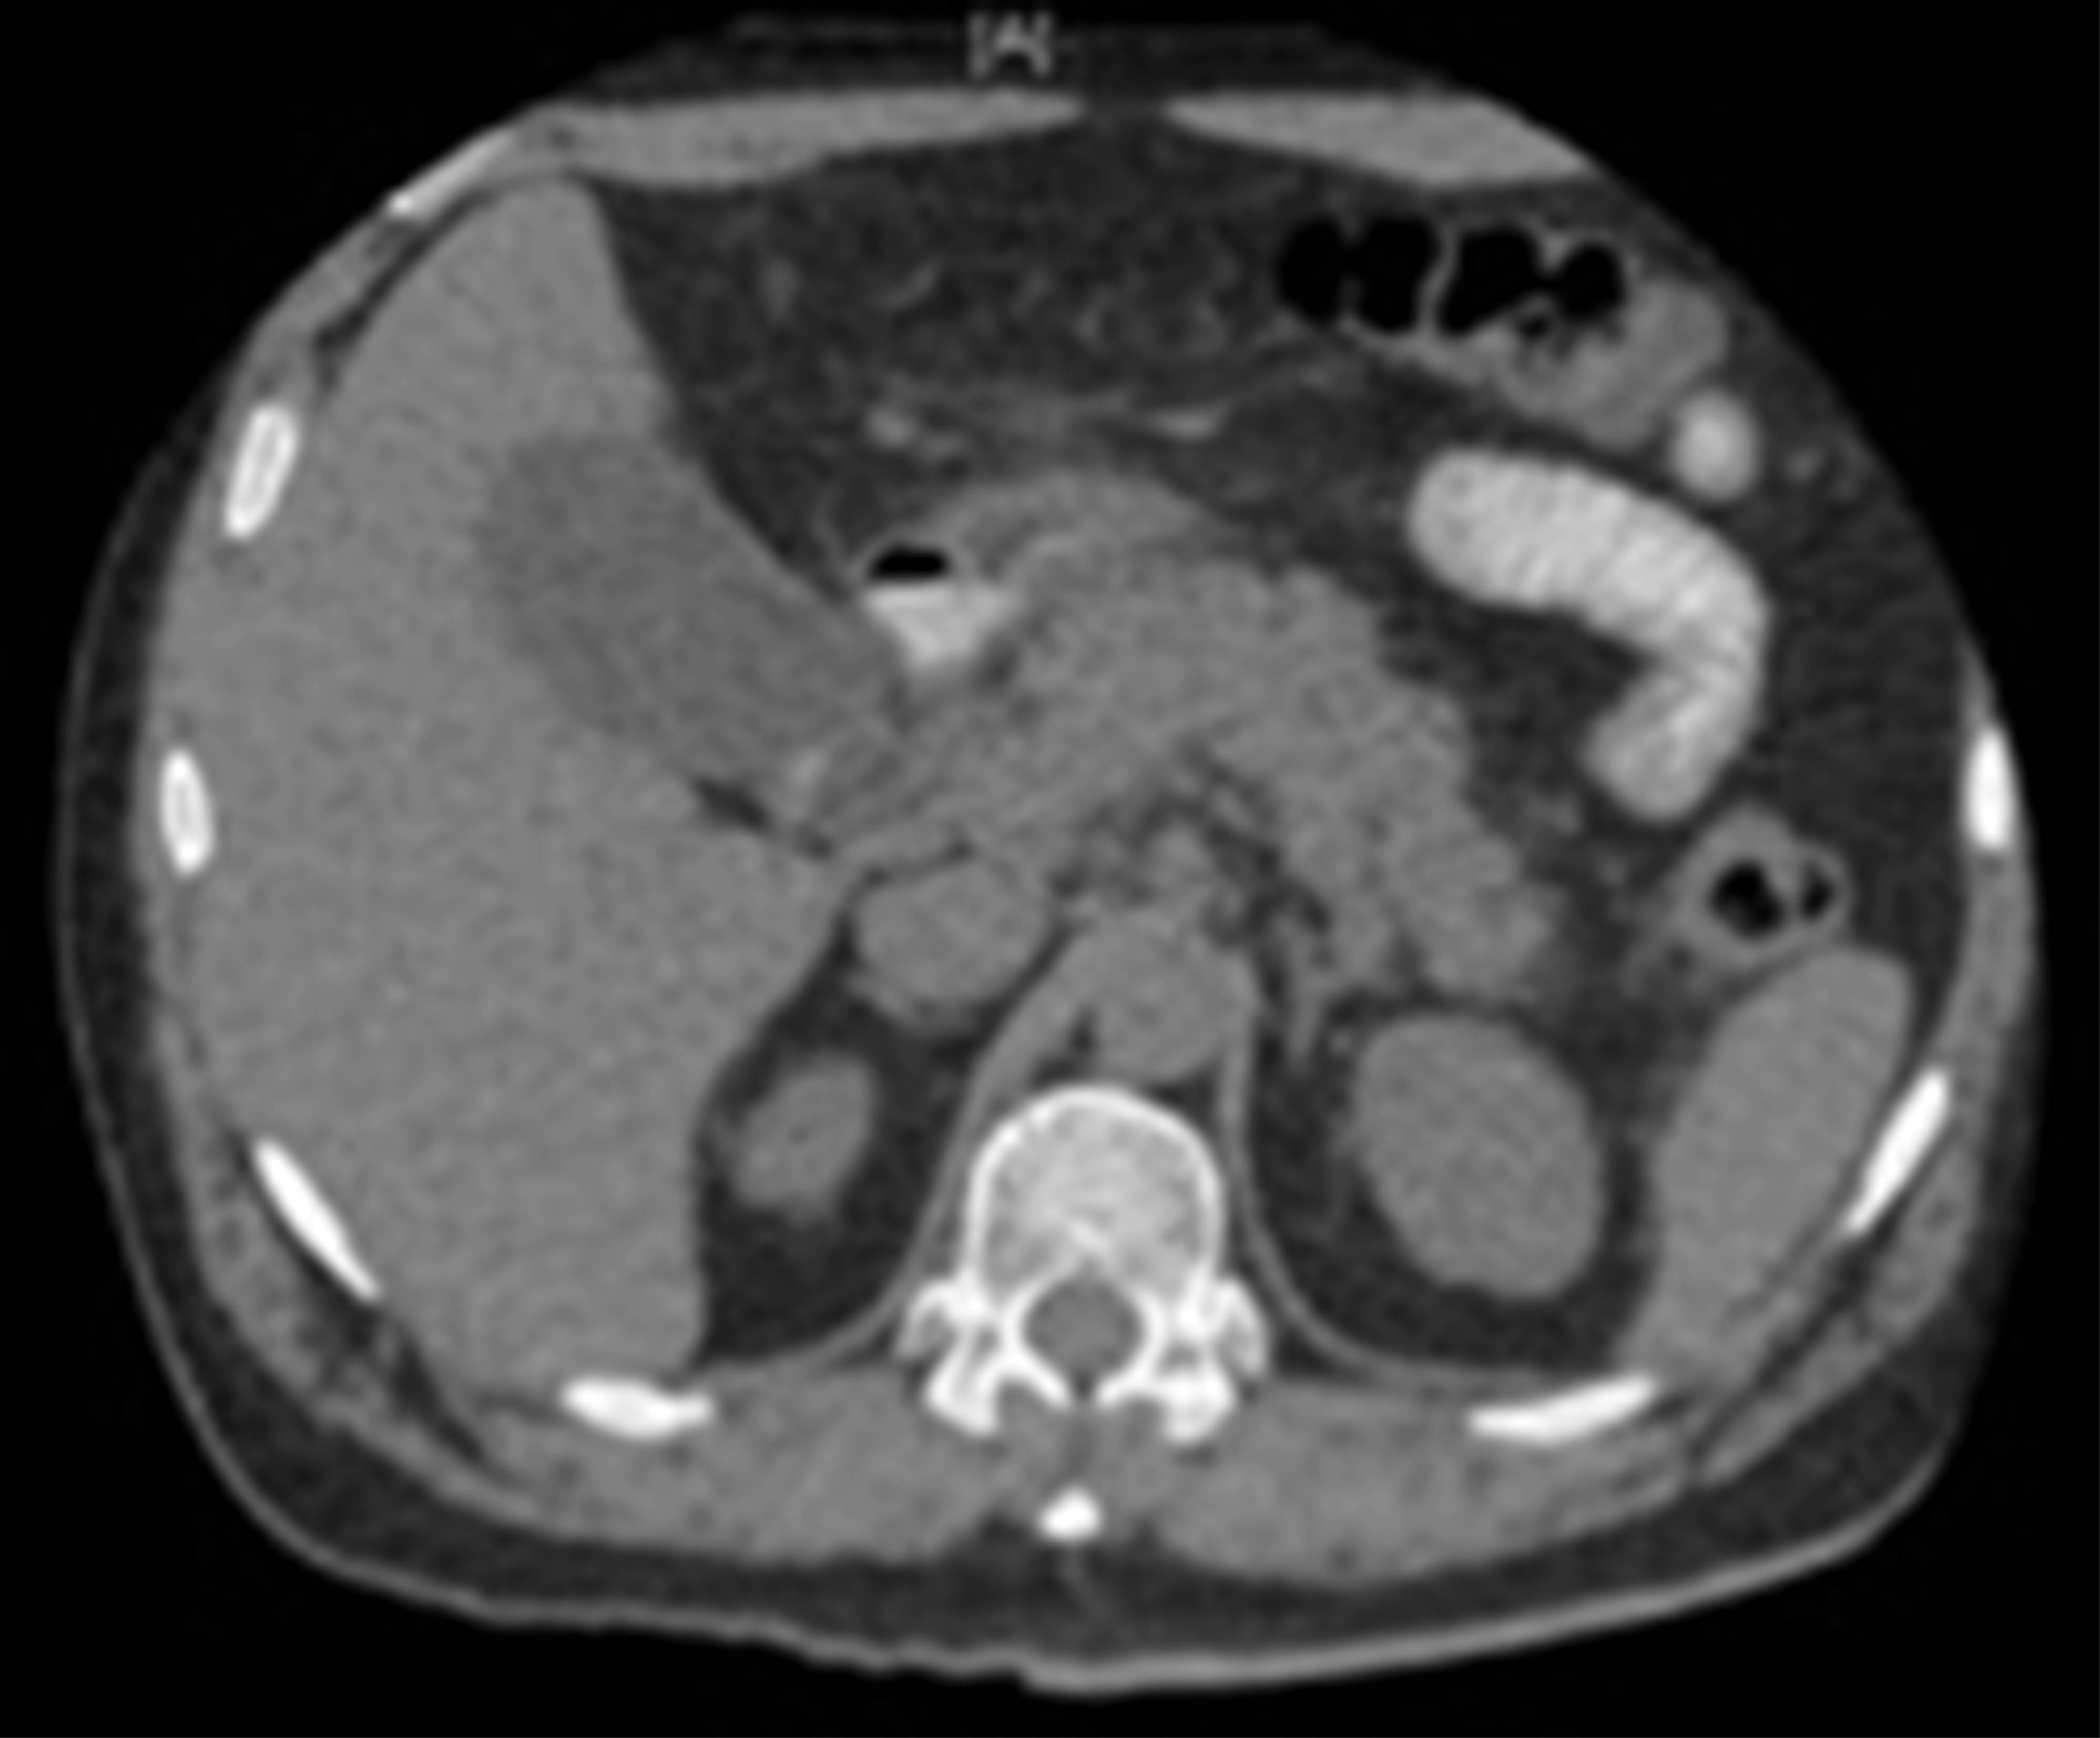

La tomografía axial computarizada (TAC) muestra pancreatitis con Balthazar B, colecistitis aguda alitiásica. Colédoco dilatado hasta 8 mm sin evidencia de litos en su interior. Con diagnóstico de pancreatitis aguda leve Ranson 1, Bedside Index for Severity in Acute Pancreatitis (BISAP) 1 (Figura 1).

Figura 1